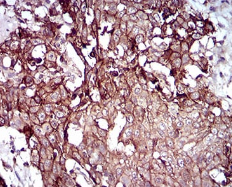

IHC    1/200 - 1/1000